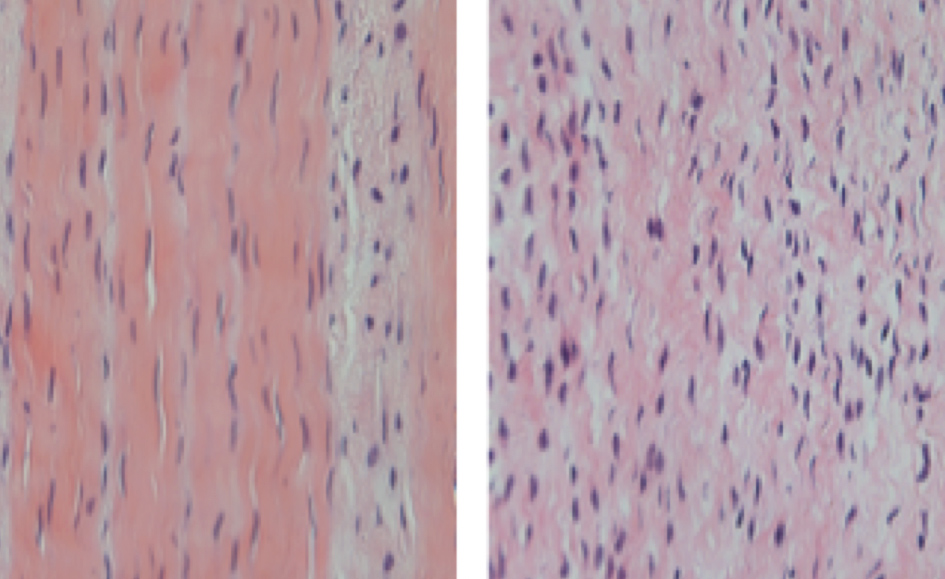

Figura 3: Imagem de microscopia óptica, corada com hematoxacilina e eosina, demonstrando aumento da celularidade do tecido a direita, característica da tendinopatia.